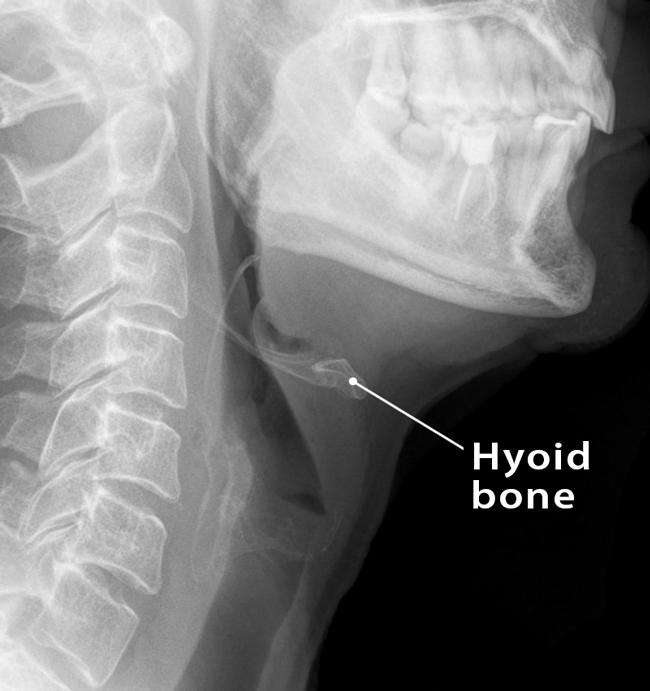

Hyoid bone

Sometimes appears as a ghost image above the mandible